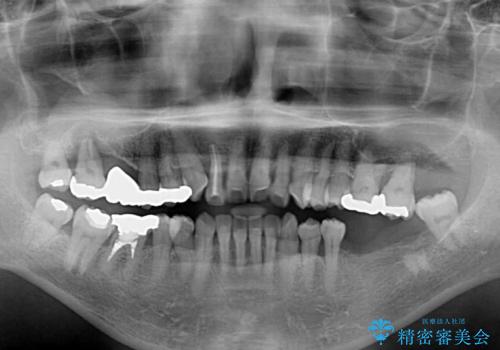

- 歯の欠損や歯肉からの出血などを気にして来院された患者様です。

診査の結果、歯周病であることが分かり、抜歯が必要な歯も見受けられました。

骨造成やインプラント、歯周外科、歯肉移植、矯正など、多くの処置を組み合わせて治療を行うこととしました。